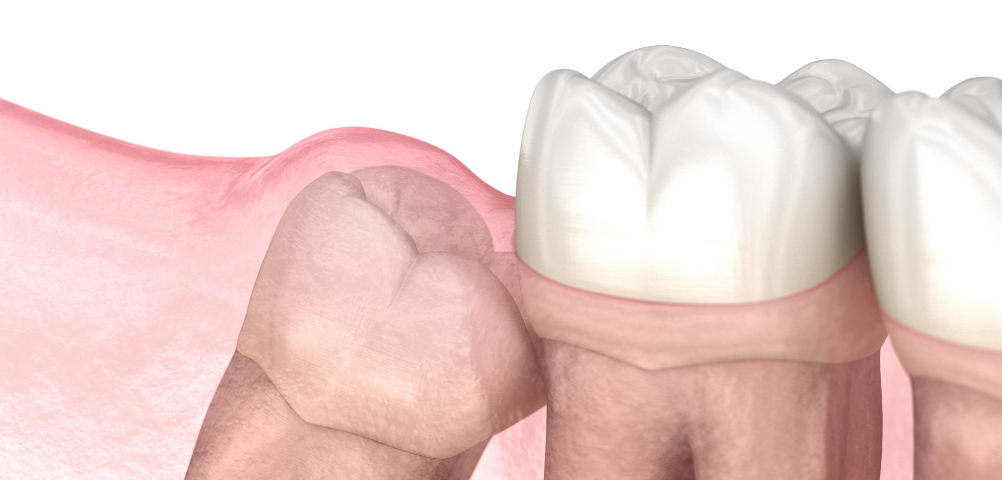

在通过锥形束CT精细确认智齿方向,

神经位置及与邻牙关系后,

仅在

确有必要的情况下才进行拔除

采用最大程度减少组

织损伤的方式来降低负担,

帮助患者更轻松地完成术后恢复